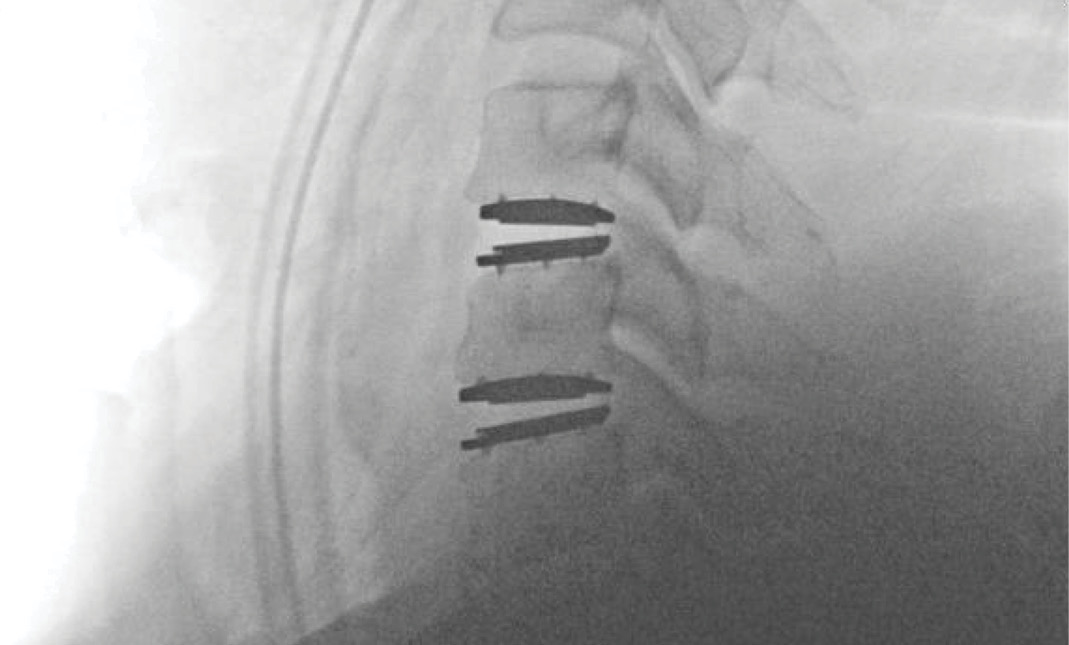

Upon examination, the patient had good motion on flexion-extension, so fusion was not considered at all. My operative plan was to use prodisc cervical devices and replace both discs at C4-5 and C5-6, giving me the flexibility to use either a domed or flat implant.

During the procedure, prodisc C Vivo fit well within the C4-5 concave endplate. I expected to use a flat endplate prodisc C SK at C5-6, however I trialed the domed prodisc C Vivo and it actually looked good, so I unexpectedly used matching implants.